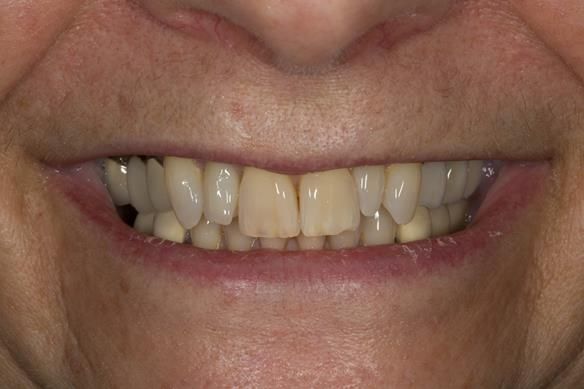

This newsletter describes in step by step detail Angela's transition through immediate partial dentures to crown supported definitive metal based dentures.

This 58 year old woman was referred to me by her general dental practitoner for treatment.

- Generalised Periodontitis; Stage 4, Grade C, Currently Unstable. Risk Factors: Type 1 diabetes. 16, 17 - hopeless prognosis. 14, 24, 26, 27, 34, 37, 44 - guarded prognosis

- Poor marginal fit and poor appearance of crowns and bridgework

- Yellowing teeth

The clinical situation and treatment process is shown in detail below with photographs. I (Finlay Sutton) provided the clinical work and Rowan Garstang provided the technical work.